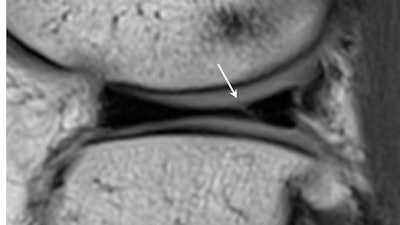

Knee protocols include sagittal, coronal, and axial combination of high-resolution proton density fat-saturated and proton density sequences of no greater than 3-mm slice thickness. Dunn underlined that small degenerative tears in the anterior horn of the lateral meniscus may be a common subclinical finding and do not usually raise concerns for the referring clinician. However, larger, potentially displaceable tears of the posterior horns could progress more suddenly, requiring arthroscopic repair or resection and affecting an athlete's playing time.

Images often depict chronic, small, healed tears that are clinically stable. "These demonstrate intermediate signal on T2 or intermediate weighted MR sequences, and should not be misread as active tears," he wrote.